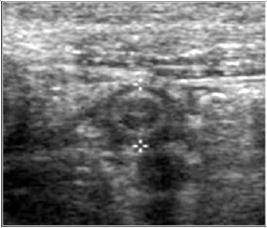

Compresia gradata sonografica este sugestiva pentru stabilirea cu acuratete a diagnsticului de apendicita. Apendicele apare ca o terminatie oarba, un fragment intestinal neperistaltic, cu originea la nivelul cecului. Printr-o compresiune maximala, se masoara diametrul antero-posterior al apendicelui. Testul este considerat pozitiv daca diametrul antero - posterior al apendicelui necomprimat este de 6 mm sau mai mult. Prezenta unui apendicolit stabileste diagnosticul. Imaginea ecografica a unui apendice normal, care este o structura tubulalara inchisa la un capat, usor compresibila, cu un diametru de 5 mm sau mai putin, exclude diagnosticul de apendicita acuta. Studiul este considerat negativ daca apendicele nu se vizualizeaza si nu exista o masa tumorala sau fluid pericecal. Cand se exclude ecografic diagnosticul de apendicita acuta, o scurta evaluare a restului cavitatii abdominale ar fi de preferat pentru stabilirea unui alt diagnostic. La femeile active sexual, organele pelvine genitale ar trebui vizualizate atat transabdominal, cat si transvaginal, pentru a exclude o patologie ginecologica care ar putea cauza durerea abdominala acuta.

Diagnosticul ecografic al apendicitei acute are o sensibilitate de 78 - 96 % si o specificitate de 85 - 98 %. Ecografia poate fi realizata in scop diagnostic la copii si femeile insarcinate, desi aplicabilitatea ei este oarecum limitata in ultimele luni de sarcina.

Ecografia are o serie de limite nete si rezultatele sunt dependente de experienta celui care o efectueaza. O imagine fals pozitiva poate sa apara in prezenta unui proces inflamator periapendicular determinat de inflamatia tesuturilor limitrofe; o dilatare a trompelor uterine poate fi confundata cu o inflamatie apendiculara, resturi de fecale neevacuate pot mima un apendicolit, iar la pacientii obezi, apendicele poate fi incompresibil atat datorita procesului inflamator acut, dar si datorita stratului de tesut adipos. Ecografii fals negative pot sa apara in conditiile unei limitari a procesului inflamator la varful apendicelui, in apendici cu localizare retrocecala, atunci cand este marit si poate fi confundat cu intestinul subtire sau in caz de perforatie apendiculara cand este comprimat.

Fig. 12 Apendicita acuta ( diametru transvers >6mm